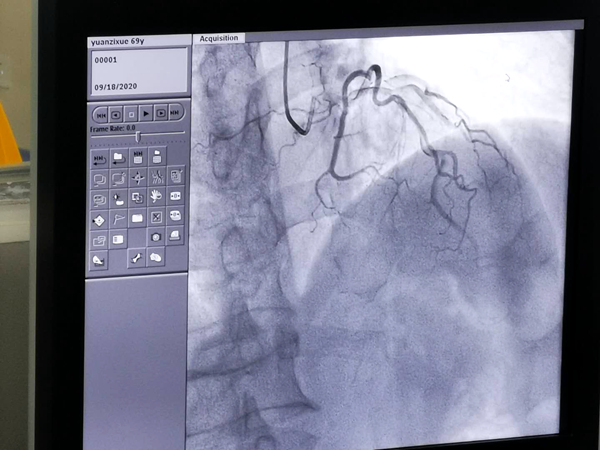

9月18日,我院介入中心成功完成4列介入治疗手术,标志着我院介入中心正式投入运行,这在全市中医类医院中也是首开先河。

医院心血管内科主任陈太军介绍,新引进的飞利浦高端平板血管造影机技术是目前十分先进的技术,在各类血管类疾病的诊断、微创介入治疗等方面都具有强大功能和划时代意义,例如在诊断方面清晰的影像质量、强大的录图功能等,能让诊断结果更快更准,在治疗上比方说支架放置是否达到最佳膨胀结果等都能清晰掌握、随时调整,对冠心病、糖尿病等疾病的检查治疗具有微创、准确、省时、仅须局部麻醉等特点。